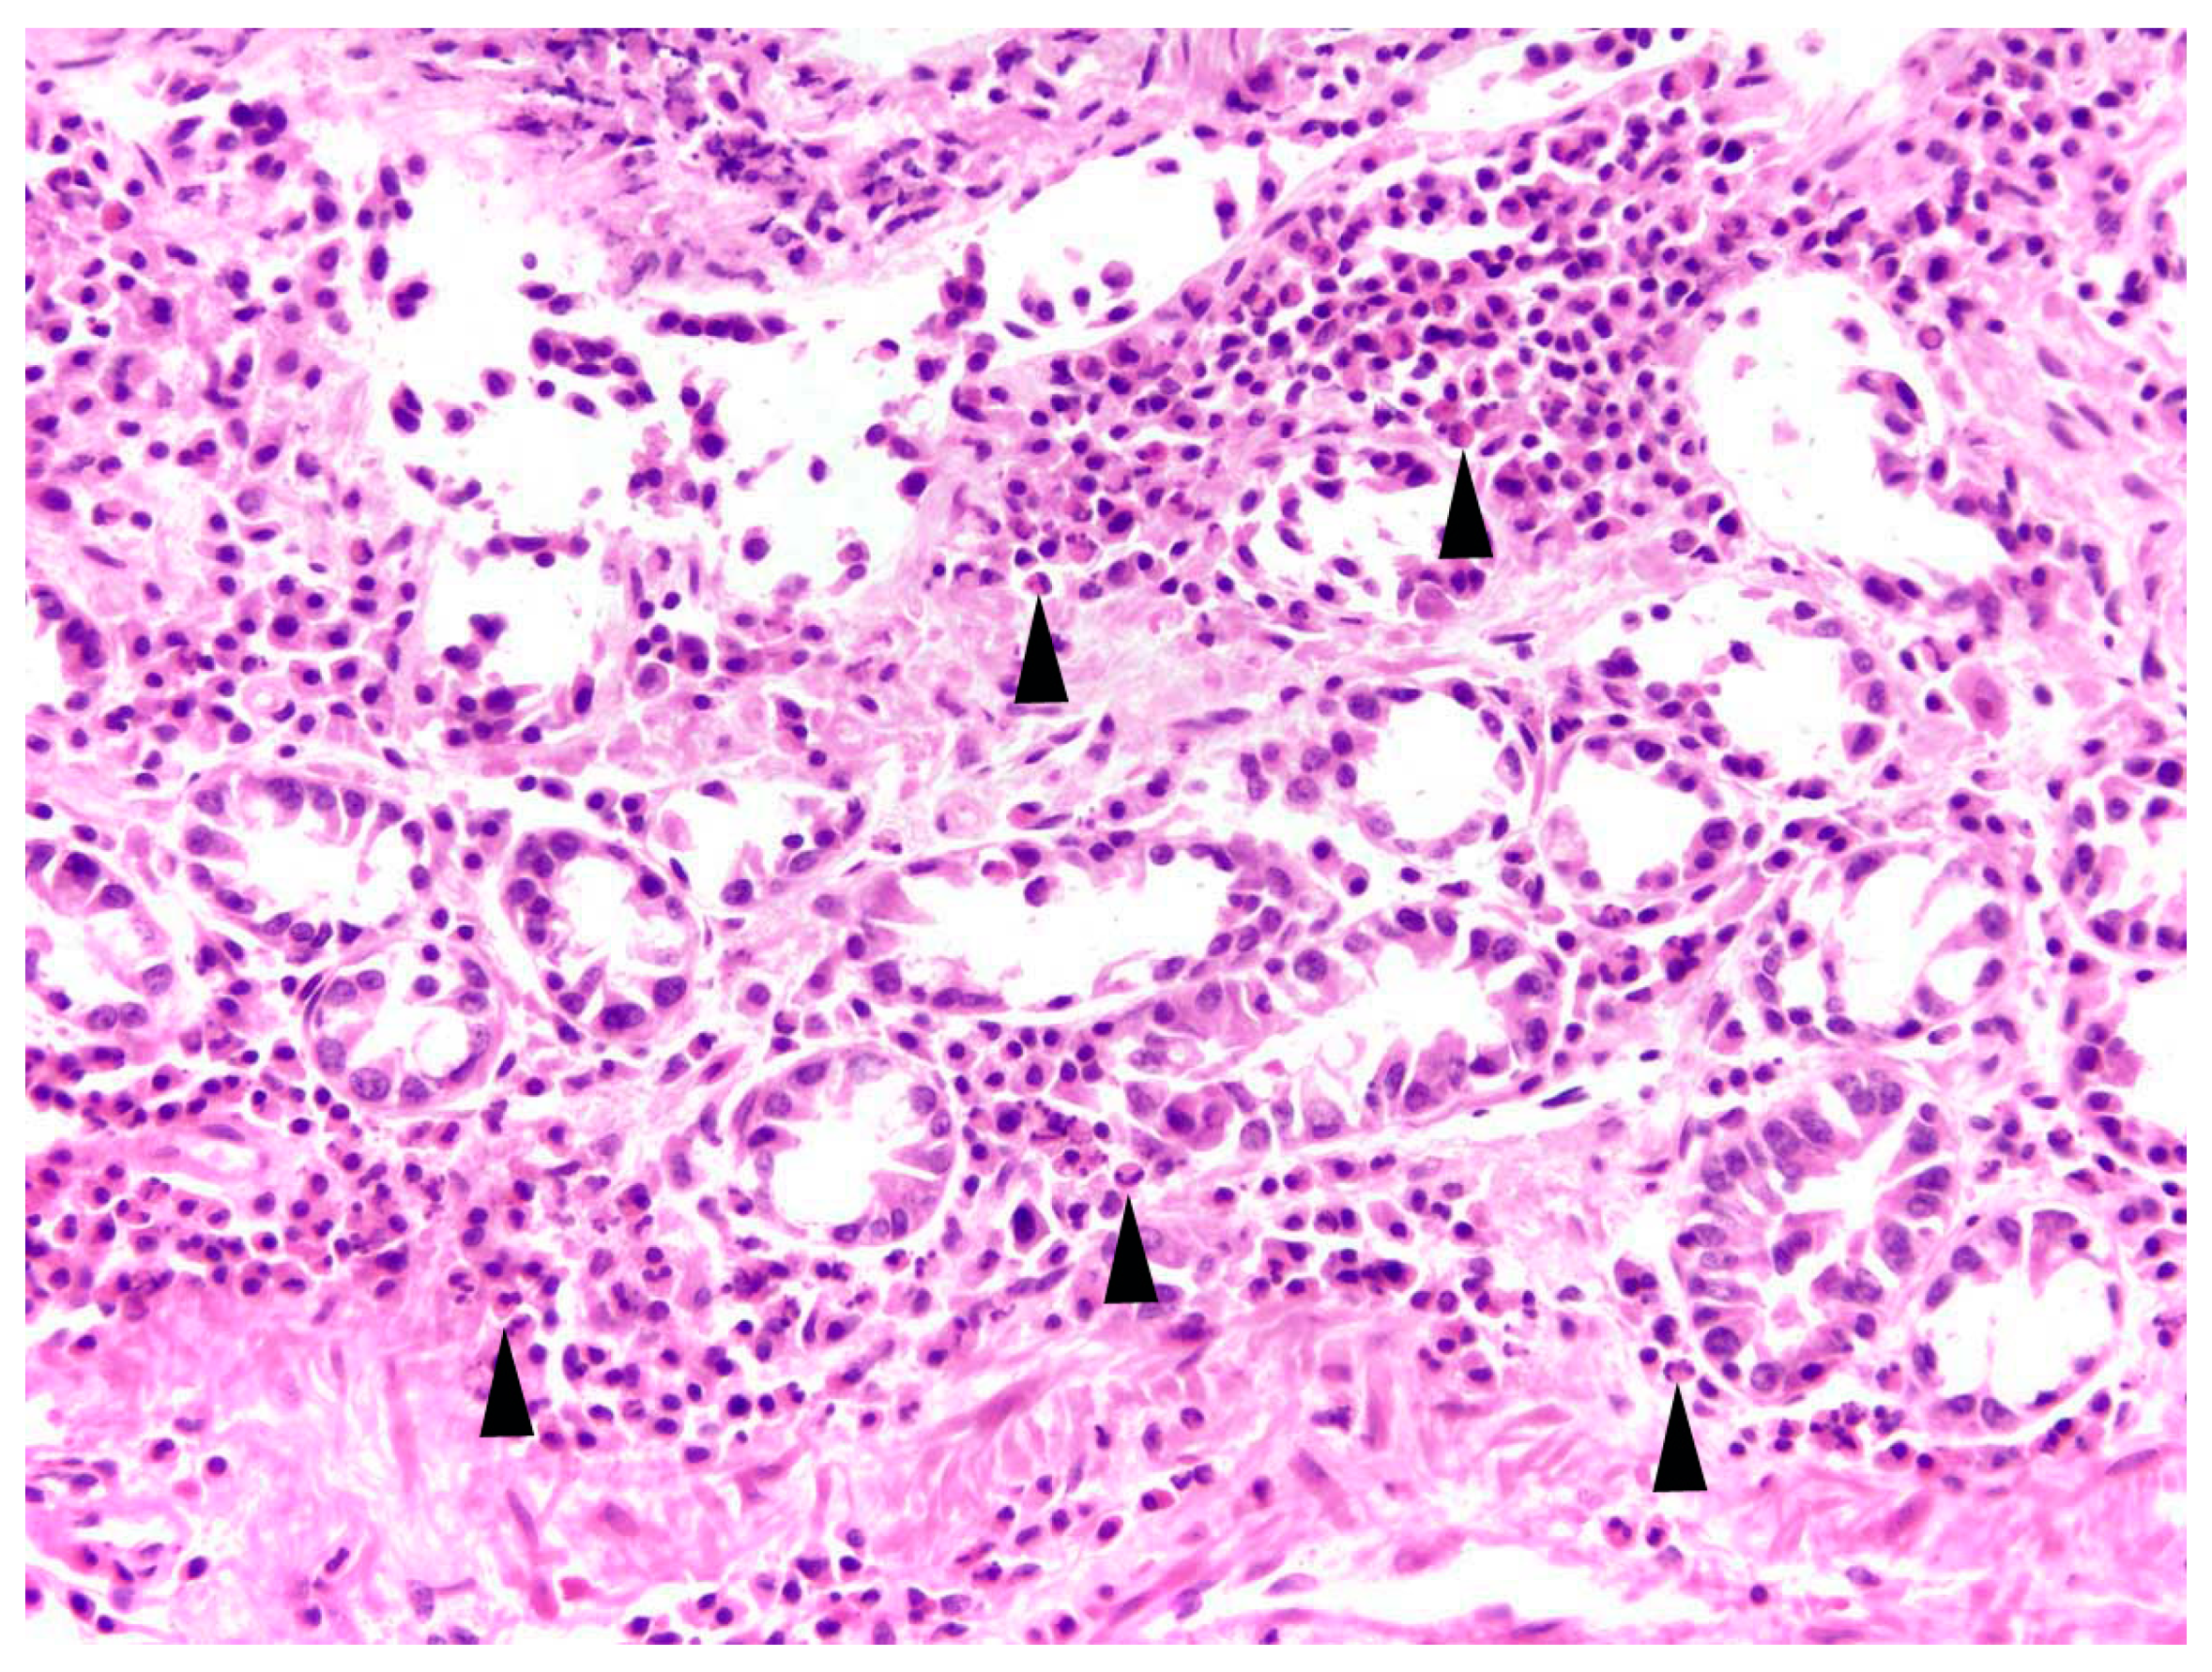

Intestine: The most common finding in histopathological analyses, which was observed in 99 out of 155 investigated hares (63.9%), was the detection of parasites or parasite stages in the intestine. Mainly different stages of protozoal organisms were found (74.7%, n = 74) and either detected in the intestinal epithelium (n = 35, Figure 5) or in the intestinal lumen (n = 19).

The presence of parasites or parasite stages in the intestine was significantly affected by the interaction of sex and age (p = 0.048; Table S1). Parasites were detected significantly more frequently in male juveniles than in male adults (post-hoc test, p = 0.038; Table S2; Figure 6).

In 20 animals (20.2%), enteritis and parasites or parasite stages were detected simultaneously in histopathological investigations.

An activation of the regional immune system in the form of hyperplasia of mesenteric lymph nodes or Peyer’s patches was diagnosed concurrently with intestinal parasites in 47 hares (47.5%).